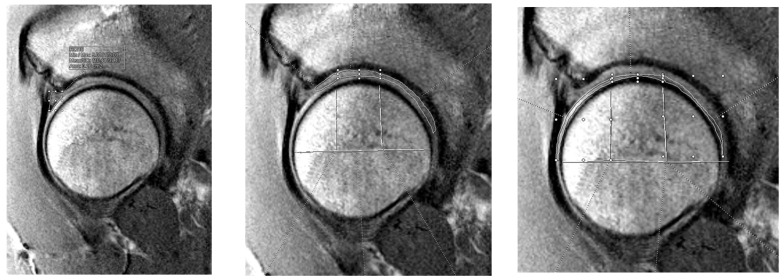

本研究评估术前软骨质量(通过T2测绘测量)与患者报告的唇裂治疗后预后之间的关系。我们回顾性回顾了14-50岁接受初级髋关节镜手术进行唇部修复或重建的患者。术前股骨、髋臼和唇部组织的T2值通过MRI进行盲法评估。国际髋关节预后工具(iHOT-12)评分收集术前和术后2年。使用单变量混合线性模型分析T2值与iHOT-12评分之间的关系。纳入29例患者(平均年龄32.5岁,BMI 24 kg/m2,女性48.3%,22例修复)。在所有患者中,T2值越高,基线和术后早期时间点iHOT-12评分越高(软骨组为3个月,唇状部为6个月;p < 0.05)。T2值越低,所有结构患者12个月和24个月iHOT-12评分越高(p < 0.001)。在修复和重建亚组中也观察到类似的趋势,延迟的负相关与较差的组织质量相关。T2映射与iHOT-12评分呈时间依赖性相关性,表明较差的软骨或唇部质量预示较差的长期预后。这些发现支持T2定位作为髋关节保留手术术前预后预测工具的实用性。

This study evaluates the relationship between preoperative cartilage quality, measured by T2 mapping, and patient-reported outcomes following labral tear treatment. We retrospectively reviewed patients aged 14-50 who underwent primary hip arthroscopy with either labral repair or reconstruction. Preoperative T2 values of femoral, acetabular, and labral tissue were assessed from MRI by blinded reviewers. International Hip Outcome Tool (iHOT-12) scores were collected preoperatively and up to two years postoperatively. Associations between T2 values and iHOT-12 scores were analyzed using univariate mixed linear models. Twenty-nine patients were included (mean age of 32.5 years, BMI 24 kg/m2, 48.3% female, and 22 repairs). Across all patients, higher T2 values were associated with higher iHOT-12 scores at baseline and early postoperative timepoints (three months for cartilage and six months for labrum; p < 0.05). Lower T2 values were associated with higher 12- and 24-month iHOT-12 scores across all structures (p < 0.001). Similar trends were observed within the repair and reconstruction subgroups, with delayed negative associations correlating with worse tissue quality. T2 mapping showed time-dependent correlations with iHOT-12 scores, indicating that worse cartilage or labral quality predicts poorer long-term outcomes. These findings support the utility of T2 mapping as a preoperative tool for prognosis in hip preservation surgery.